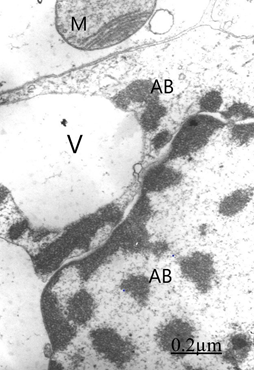

We found swollen and ischemic neurons and glial cells leading to nerve cell death types, such as apoptosis, oncosis, autophagic cell death leading to necrosis (Figure 5).16, 17 Astrocyte exhibiting apoptotic cell death type showing apoptotic bodies in nucleus and cytoplasm (Figure 6). Morphopatological changes of dendrites17 and dendritic spines18,19 are observed. The dendrites show a beaded shape, vacuolization, edematous mitochondria and cytoskeletal disruption (Figure 7). Dendritic postynaptic spines appear swollen and contain an atrophic spine apparatus. They are observed making axospinodendritic synapses (Figures 8&9).

Figure 6 Brain trauma, hematoma subdural. Astrocyte cell showing apoptotic bodies (AB) in nucleus (N) and cytoplasm. A swollen and degenerated mitochondrion (M) also is seen.